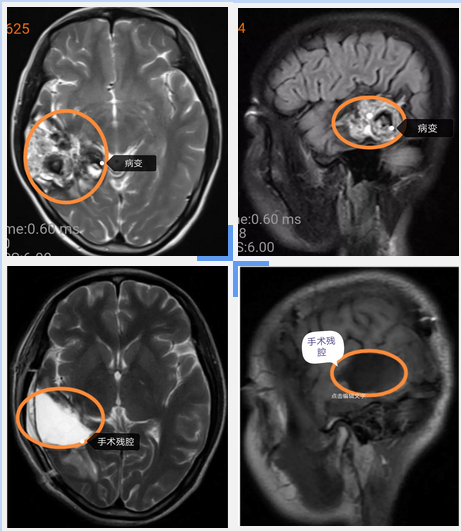

三個月前她突然出現(xiàn)頭痛,到當?shù)蒯t(yī)院就診,頭顱CT檢查:右顳葉團片狀異常密度影。頭顱磁共振增強檢查:右側顳枕葉占位。初步診斷:右顳枕葉占位,首先考慮顱內海綿狀血管瘤,不能排除膠質瘤可能。

考慮顱內占位的基底部深在,緊貼腦干及丘腦等重要功能區(qū),經(jīng)過詳細的檢查,術前的認真準備,在手術室的全力配合下,順利在顯微鏡下完成病灶全切,術后通過神經(jīng)外科全體醫(yī)護人員的精心治療和護理,患者恢復良好,順利出院,露出了久違的笑容。住院總費用5萬元左右,術后病理報告提示:腦血管畸形伴出血。

臨床上CT(計算機斷層掃描)和MRI(磁共振)是臨床診斷顱內海綿狀血管瘤的常用方法。本病為良性疾病,預后良好。手術治療能有效地防止出血和控制癲癇的發(fā)作,術后能夠恢復正常的工作或學習。